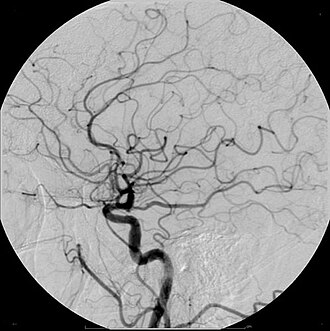

Digitalna subtrakcijska angiografija

Digitalna subtrakcijska angiografija je radiološka tehnika